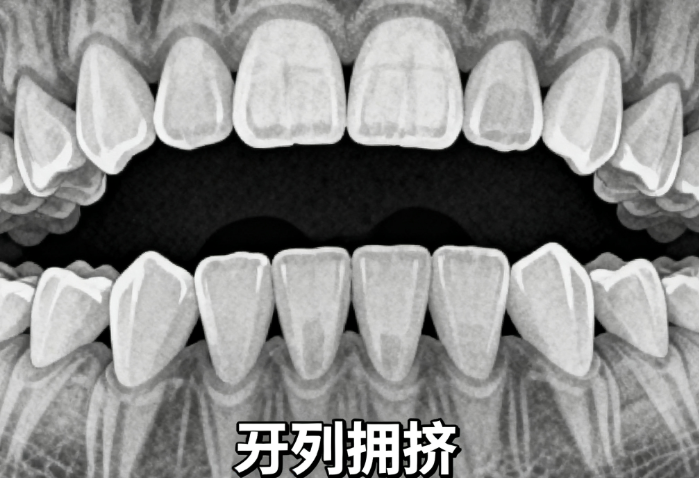

2、正畸項(xiàng)目價(jià)格親民

金屬托槽五千五起,適合學(xué)生黨或者預(yù)算有限的年輕人;隱形矯正時(shí)代天使一萬八千九起,隱適美三萬五起,雖然貴點(diǎn)但美觀度高,不影響社交。